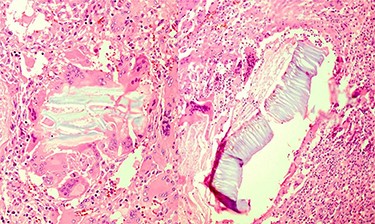

Multinucleated foreign body-type giant cells and inflammatory cells surrounding the vegetable fibers.

Portions of the gastric wall with acute and chronic inflammation were received. Fat necrosis, foreign body-type giant cells, granulomatous formation and fibroblastic proliferation in serosal and perigastric fat were observed, which had infiltrated submucosa in some areas and were attached to the liver tissue (vegetable fibers component?).

Perigastric fat tissue also shows acute and chronic inflammation, fat necrosis and foreign body-type granulomatous formation.

Omentum shows focal foreign body-type granulomatous formation (Fig. 3).